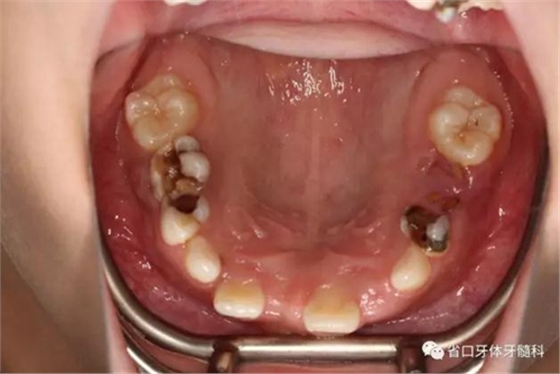

口內(nèi)情況:牙合 面觀